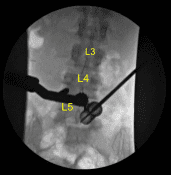

A 22-gauge spinal needle was used to localize the L5-S1 level. A marking pen was used to demarcate the midline. An 18 mm vertical incision adjacent to the spinous process on the right side was demarcated. 1% lidocaine with epinephrine was infused.

The skin was opened with a #15 blade scalpel. Hemostasis was obtained with Bovie. Bovie was used to sharply divide the fascia. Sequential dilators were used to dock a 16 mm diameter x 4 cm tubular retractor which was affixed rigidly to the bed frame.